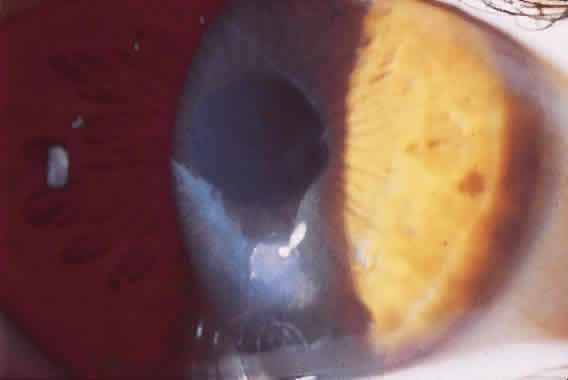

Until the epithelium completely heals, the risk of postoperative infection is greatest. Post-RK bacterial keratitis is primarily the result of the break in epithelial barrier created by the incisions. Adherence of causative organisms to the denuded epithelium over radial incisions can lead to infectious keratitis (Fig. 2). Recently, Panda and colleagues11 highlighted the severity of bacterial keratitis, despite its low incidence. They reported nine cases of post-RK bacterial keratitis at a tertiary-care cornea service during a 9-year period. Four of the nine cases followed primary RK and five followed enhancement procedures. Therapeutic penetrating keratoplasty was performed in one patient. Four of the nine eyes required subsequent penetrating keratoplasty, and one required lamellar keratoplasty. All but one eye retained 20/60 vision or better. These results are discouraging, but the actual incidence of bacterial keratitis lies somewhere between 0% and 0.4%.9,12–14 The PERK study found only 3 cases of bacterial keratitis in 793 eyes (0.38%); all occurred more than 7 months after surgery. All cases occurred in inferior incisions, and only one was spontaneous (one case with contact lens use and another with ocular trauma). None of the three eyes lost BSCVA. Hoffer and associates14 reported only one case of corneal ulcer after RK in 134 procedures performed at Jules Stein.

Post-RK bacterial keratitis usually occurs within 2 weeks of the procedure and is caused by virulent bacteria. The most common causative organisms are listed in Table 1. Infiltrates most commonly arise in the RK incision. Culture and Gram stain should be performed, and frequent fortified topical antibiotics that target the most common organisms should be used until the acute infection is under control. These cases of bacterial keratitis can result in significant vision loss, but if treated appropriately these infections can often be controlled with minimal reduction in vision.11,15 If the site of keratitis coincides with an area of microperforation or macroperforation, aggressive therapy and follow-up are required to avoid bacterial endophthalmitis.16–19